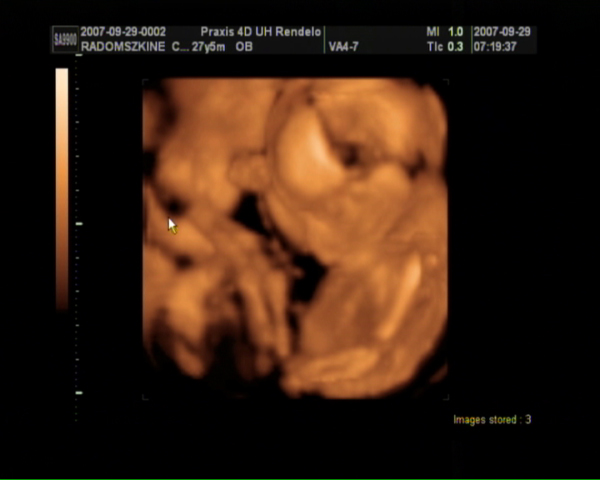

Szombaton voltunk 4D-n, tündériek a fiúk (mert kiderült, hogy 2 fiunk lesz!)! :lol:

Kép Dávid Kép Bálint